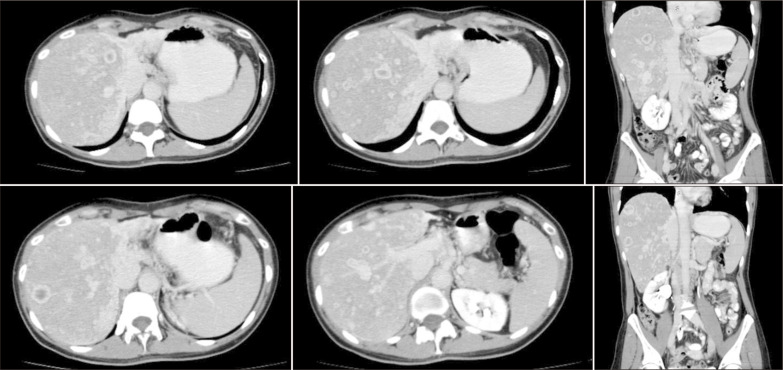

Patients with nonresectable breast cancer liver metastasis (BCLM) face a dismal prognosis. Despite liver transplantation (LT) for metastatic liver tumors having recently shown good results, BCLM represents an absolute contraindication. This study aimed to investigate the potential for long-term survival after LT for BCLMs in a patient experiencing end-stage liver disease, following multiple oncologic treatments. In July 2019, we performed a deceased donor LT on a 41-year-old female with BCLM controlled with human epidermal growth factor receptor 2 targeted therapy, who developed liver failure following multiple locoregional liver-directed treatments. The primary tumor was treated with surgical resection and adjuvant chemoradiation in 2000. The procedure was performed under a protocol approved by the local ethical committee, and by the Italian National Transplant Center. A 12-month treatment with trastuzumab was performed immediately after LT. Immunosuppression following transplantation was undertaken without steroids, and with everolimus. The patient completed 12 months of follow-up without recurrence. Trastuzumab was then withdrawn. Fifteen months after LT, a liver recurrence occurred that was treated with chemotherapy. In October 2021, she developed 2 brain lesions that were treated with stereotactic radiation. The patient is still alive, with a positron emission tomography/computed tomography performed in January 2024 showing no disease. LT for this patient with BCLM of extreme selectivity showed a good clinical outcome. Perioperative systemic treatment and tumor control are necessary. A specific protocol should be discussed within a multidisciplinary team, and with local and national authorities. Even if tumor recurrence occurs, multimodal therapy can control the disease.

Abstract Image